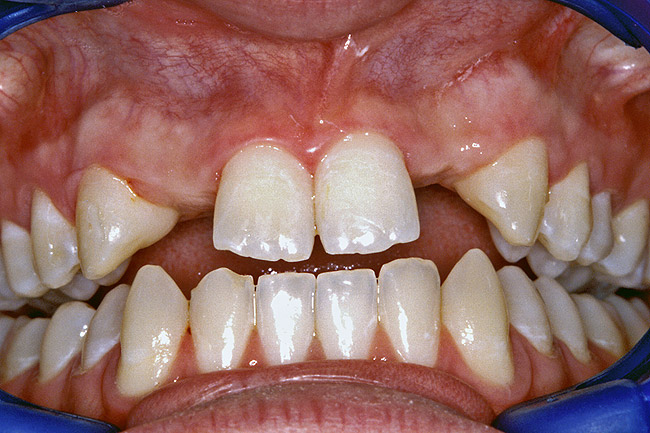

A 17-year-old boy presented with a history of congenitally missing maxillary lateral incisors. The patient had been under the care of an orthodontist for several years to manage his occlusion during his adolescent growth phase. The patient originally presented with his parents after being told that the “braces were ready to be removed, and their son was now ready for implants to replace the missing teeth.” This is not an u.common circumstance, and unfortunately the orthodontic alignment was performed before the patient was sent to the restoring dentist. Therefore, the orthodontist was not aware of the space requirements for future implant placement. This case highlights the importance of proper.communication between all members of the implant team, especially during the orthodontic planning phase. The patient’s medical history was unremarkable, and the patient was found to be healthy and a good potential candidate for dental implants to replace the missing lateral incisors.

Periapical radiographs were taken to help determine the mesial-distal inclinations of the adjacent tooth roots (Figure 1). The radiographs revealed a serious issue, convergent roots for the right canine and right central, which eliminated that area as a potential implant-receptor site. The space between the left central and canine teeth was minimal, although the roots were relatively parallel. Clinical examination (manual palpation of the root eminences superiorly to the vestibule on the right side) confirmed the root convergence (Figure 2A). The flat, wide zone of the keratinized tissue and lack of interdental papilla was evident for the missing right lateral incisor. There was a marked difference in clinical appearance for the left lateral, which could impact the eventual plan of treatment (Figure 2B). Other significant clinical findings included bilateral facial bone concavities, which existed as a result of the congenitally missing tooth roots. As a diagnostic cue to the underlying bone topography, it is important to follow the demarcation between attached and unattached gingival tissue, and note the crestal width of the available keratinized tissue (Figure 2C).

Figure 2a  Pretreatment buccal views showed (A) root convergence, (B) a difference in clinical appearance of the left lateral, and (C) significant crestal width of keratinized tissue.

Figure 2a

Figure 2b  Pretreatment buccal views showed (A) root convergence, (B) a difference in clinical appearance of the left lateral, and (C) significant crestal width of keratinized tissue.

Figure 2b

Figure 2c  Pretreatment buccal views showed (A) root convergence, (B) a difference in clinical appearance of the left lateral, and (C) significant crestal width of keratinized tissue.

Figure 2c